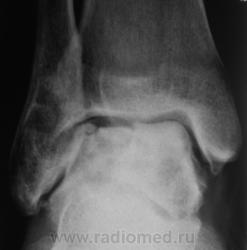

Пациент направлен на рентгенографию голеностопного сустава с диагнозом ДОА.

После внутрисуставного перелома вероятность доа оччень высока. Колгда была травма?

Травма была два года тому.

Похоже  на  остеохондропатию  блока  таранной  кости  +   ДОА.

Посттравматический артроз с кистовидной перестройкойлатерального мыщелка Субхондральное уплотнение исужение суст. щелей естьИ неконгруэнтность большеберцового эпифиза к таранной маленько просматривается?